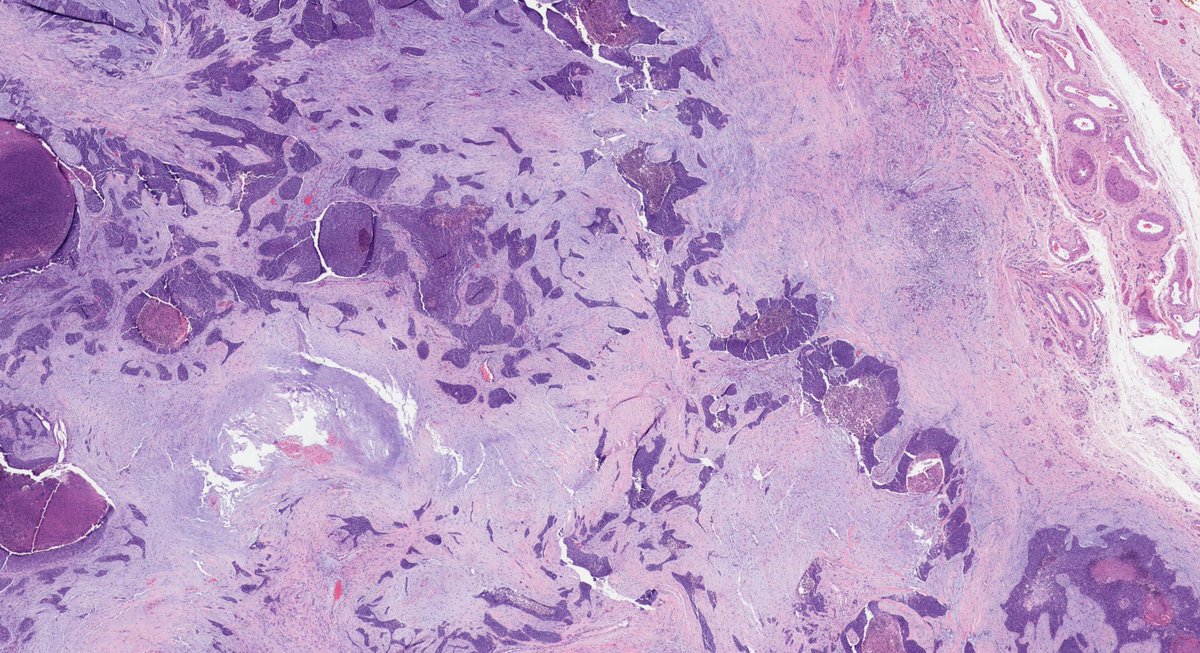

Remember leiomyosarcomas arising from vessels may be aggressive unlike leiomyosarcoma from arrector pili. This LMS arising from vein; note residual vascular wall at periphery. Residual vein top left corner on image 2 & 3. Ref: Italiano A, et al. PubMed PMID: 20167595. #dermpath

SteveBillingsMD's tweet image. Remember leiomyosarcomas arising from vessels may be aggressive unlike leiomyosarcoma from arrector pili. This LMS arising from vein; note residual vascular wall at periphery.  Residual vein top left corner on image 2 & 3. Ref: Italiano A, et al. PubMed PMID: 20167595. #dermpath